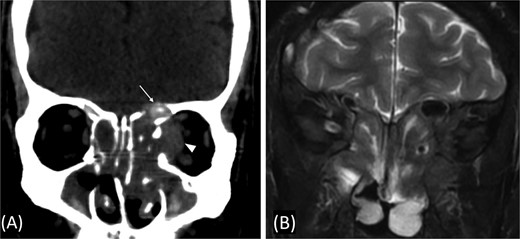

A previously healthy 36-year-old man presented to the emergency department complaining of persistent frontal headache, dizziness, and vomiting of 1 month duration, with no history of orbital complaints (e.g. visual deficits or swelling) or neurological deficits (e.g. limb weakness or seizure-like movements). On examination, the nasal endoscopy showed dry crusts filling the right nasal area. Therefore, due to the subtle symptoms’ origin, the patient was admitted, and a computed tomography (CT) scan of the head and a magnetic resonance imaging (MRI) of the brain were scheduled. The head CT scan revealed complete opacification of the maxillary, ethmoid, frontal, and sphenoid sinuses with bone destruction affecting the left lamina papyracea and roof of the ethmoid air cells (Fig. 1A). The brain MRI demonstrated similar findings with intra-orbital extension resulting in left global proptosis, which triggered concerns regarding fungal rhinosinusitis (Fig. 1B). Accordingly, the patient underwent functional endoscopic sinus surgery (FESS) with a right frontal craniotomy and partial removal of the infected brain tissue on the fourth day of his presentation. Specimens from both surgical sites were sent for pathology and cultures during the surgery. The histopathological results confirmed the diagnosis of CGIFRS, and A. flavus was found in the tissue culture. Postoperatively, the patient was stable, and intravenous antifungal treatment (amphotericin B and voriconazole) and high-dose steroid administration (dexamethasone) were started promptly following confirmation of CGIFRS via pathology. One week after the surgery, the patient’s condition suddenly deteriorated: he had a right fixed dilated pupil and spikes of fever. An urgent brain MRI with contrast was performed, which showed an intracranial abscess, and a significant midline shift to the right side (Fig. 2A and B). The patient, therefore, had a right decompression craniotomy and remained intubated and ventilated in the intensive care unit to receive the maximum medical therapy. However, despite this intensive treatment, the patient’s condition continued to worsen, and he ultimately died after 2 weeks.

(A) Paranasal sinuses CT scan without contrast showing opacification of the sinuses with hyperdense contents. It results dehiscence of the left lamina papyracea and extension in the medial extraconal space (arrowhead). The ethmoid air cells roof show dehiscence of the roof with intracranial extension (arrow). (B) Coronal T2 MRI through the posterior aspect of left orbit shows the intra-orbital extraconal extension as well as the hypointense left ethmoidal disease with extradural intracranial extension.